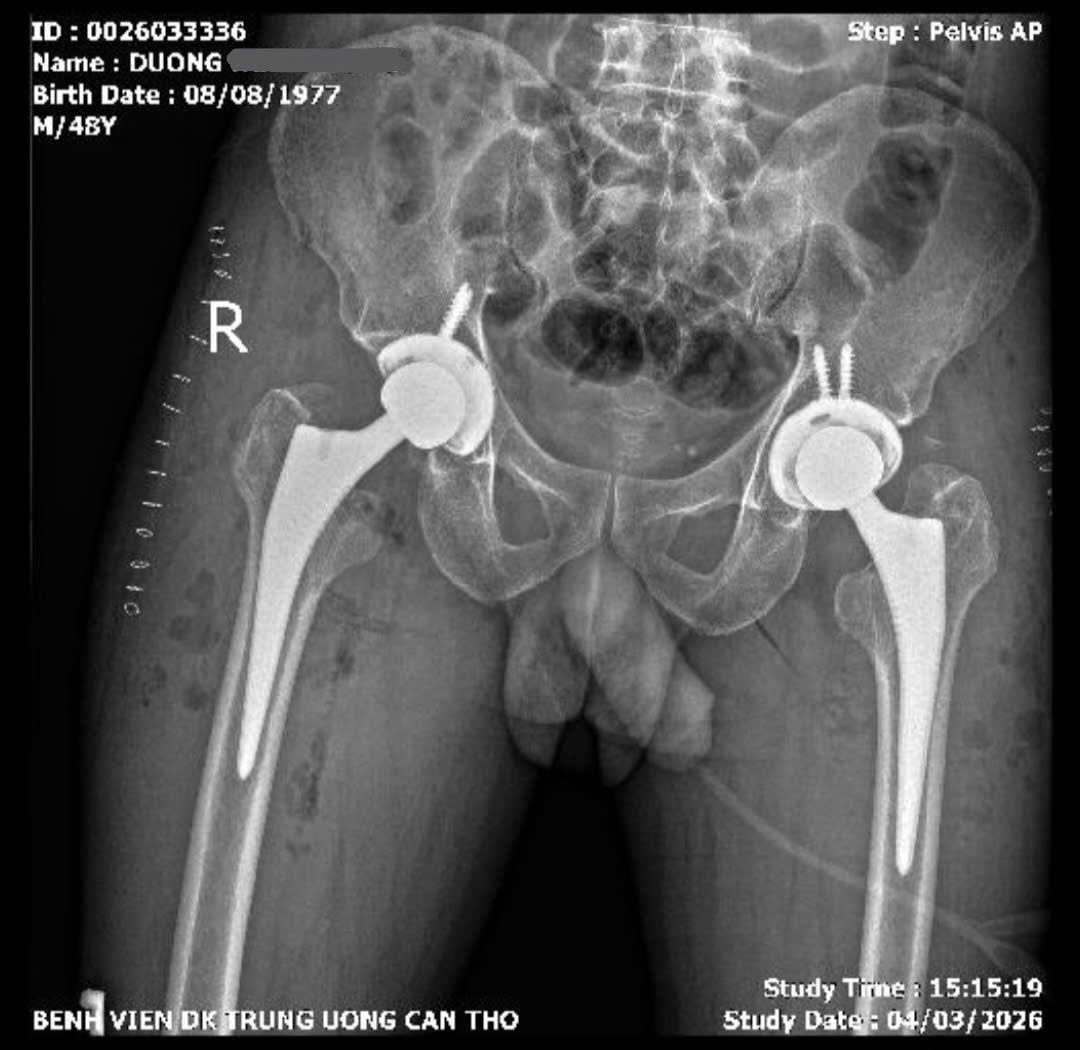

Ca phẫu thuật do BS.CKII Dương Khải, Trưởng khoa Phẫu thuật thay khớp và Ung bướu học chỉnh hình cùng ê-kíp Trung tâm Chấn thương Chỉnh hình thực hiện. Các bác sĩ lựa chọn đường mổ trực tiếp phía trước, một phương pháp phẫu thuật ít xâm lấn trong thay khớp háng. Ca mổ kéo dài khoảng 4 giờ và tiến hành thay khớp háng hai bên trong cùng một lần phẫu thuật.

Sau mổ, bệnh nhân phục hồi thuận lợi; đến ngày thứ hai đã có thể tập đi lại với khung hỗ trợ và sau 5 ngày có thể tự đi lại không cần dụng cụ hỗ trợ. Dự kiến bệnh nhân sẽ được xuất viện vào ngày 11/3.